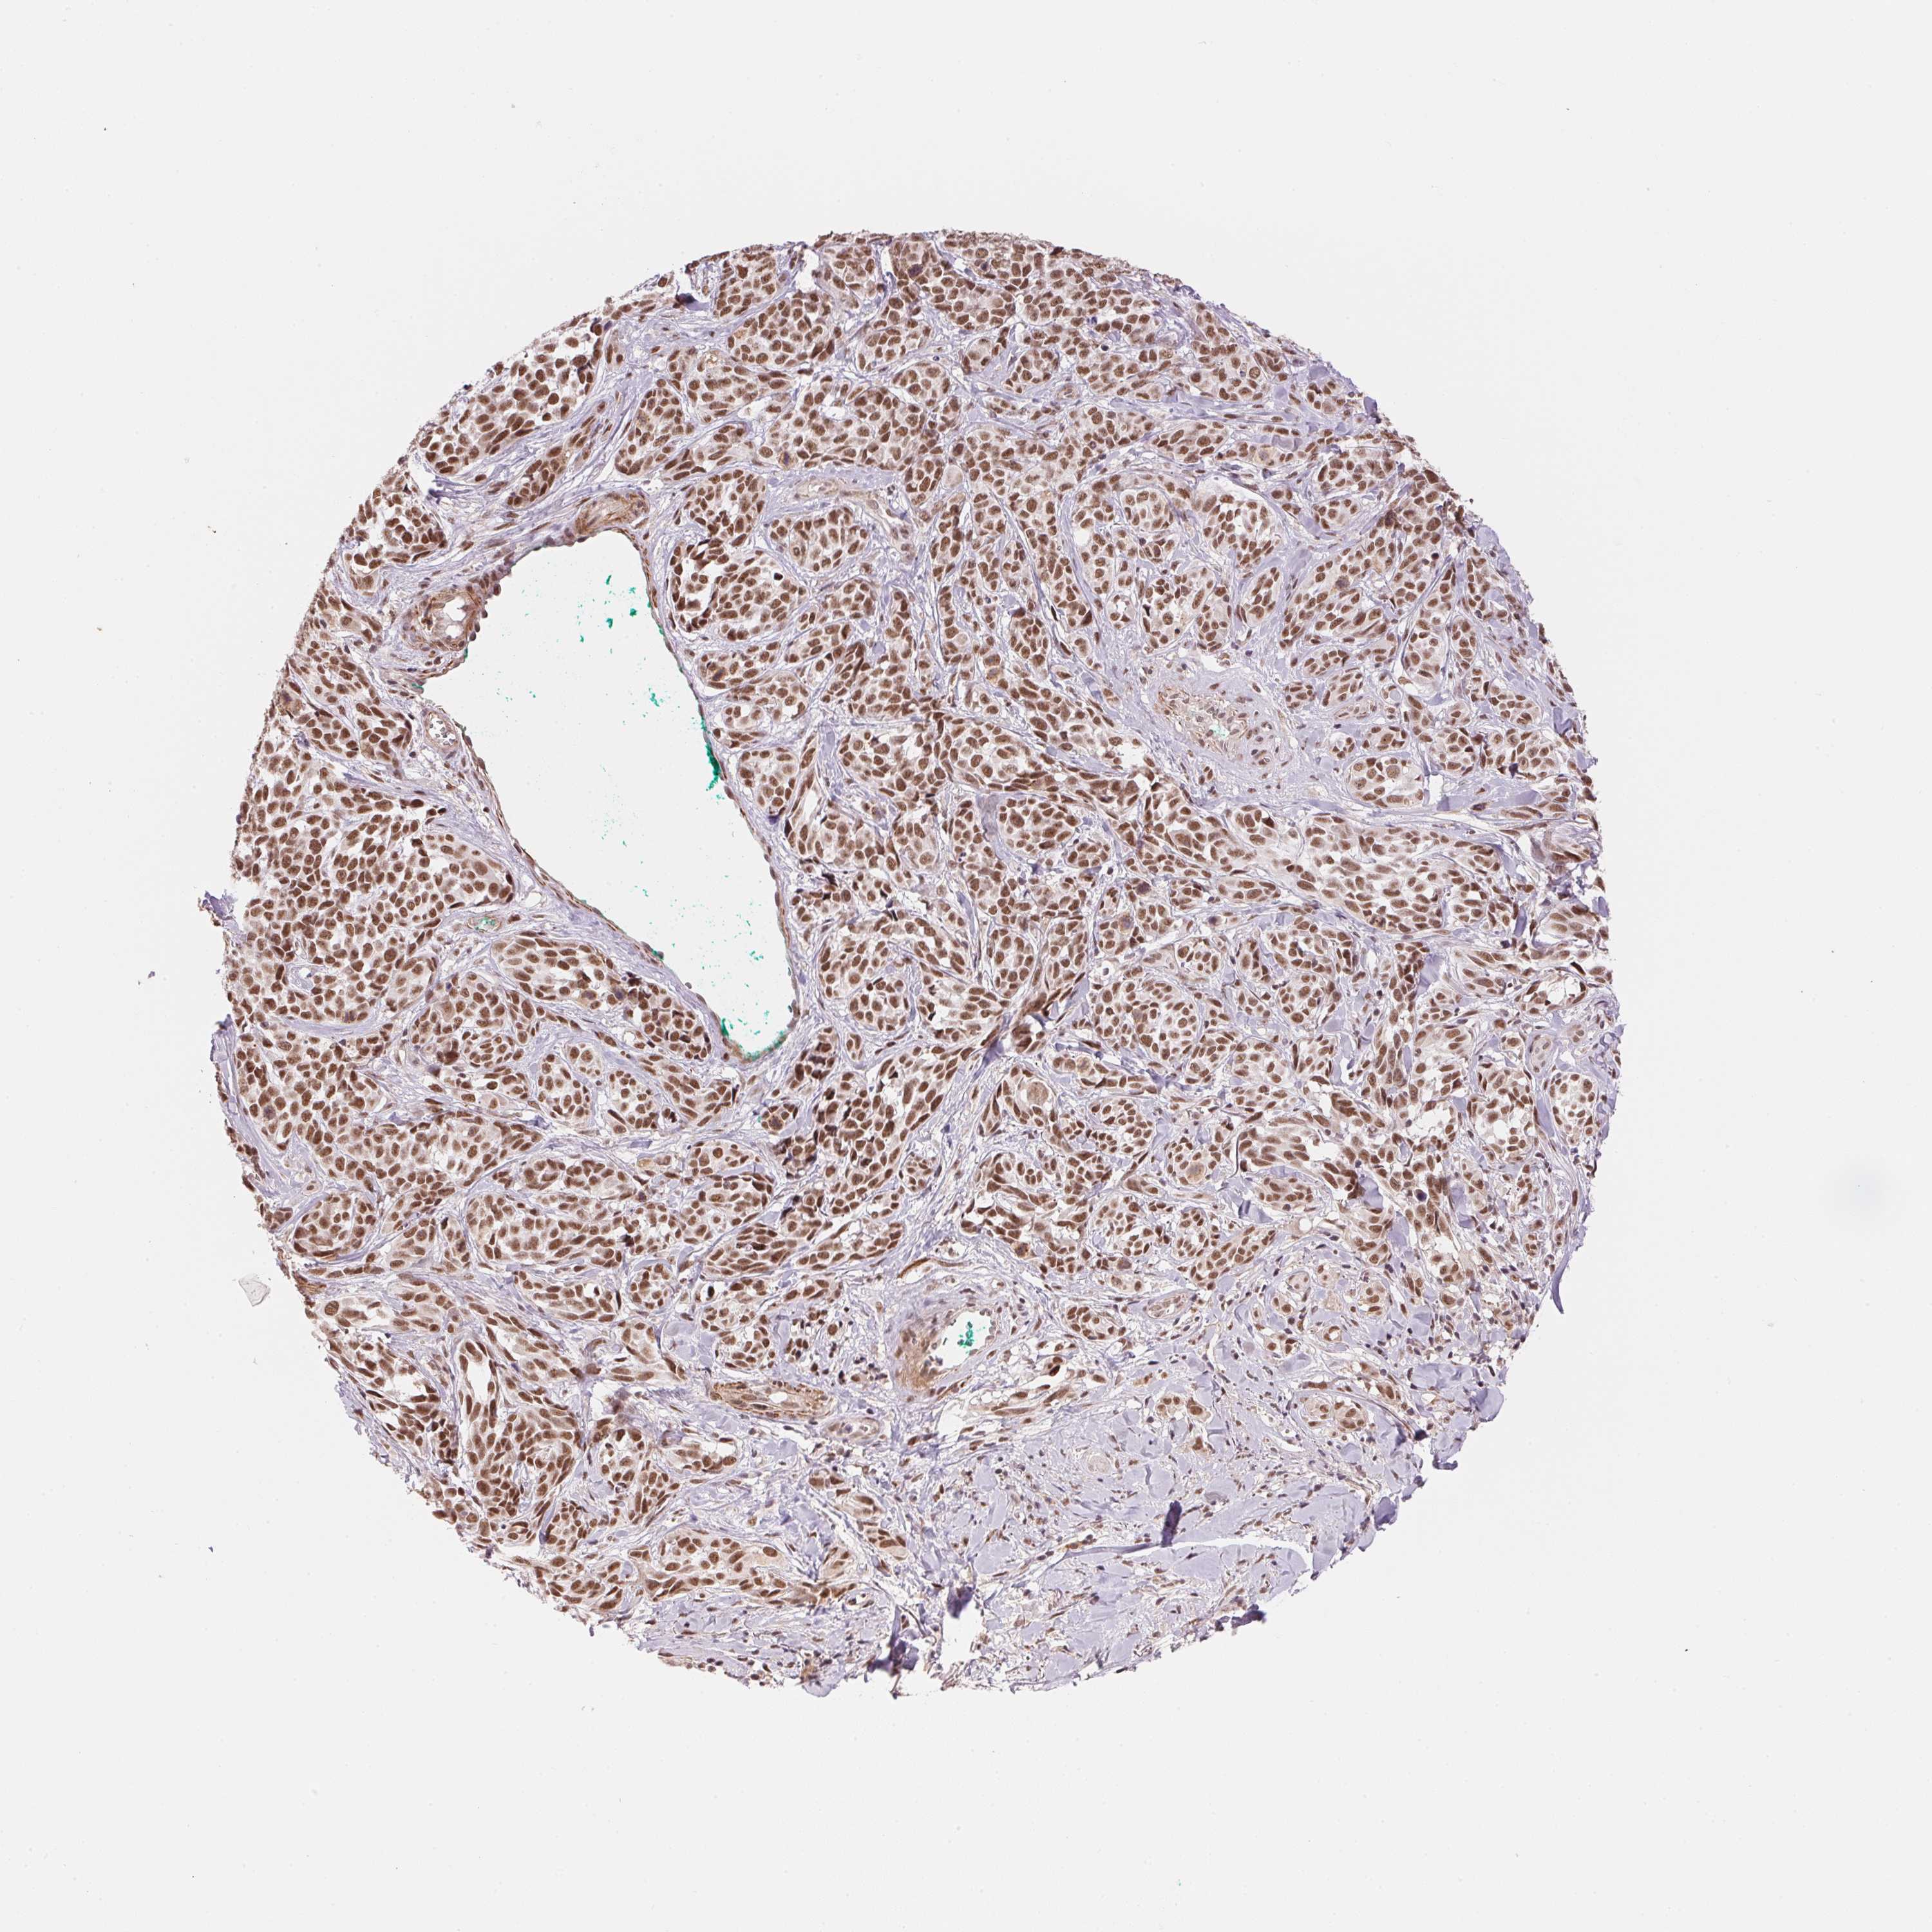

MELANOMA - Protein expressioni

A mouse-over function shows sample information and annotation data. Click on an image to view it in a full screen mode. Samples can be filtered based on level of antibody staining by selecting one or several of the following categories: high, medium, low and not detected. The assay and annotation is described here.

Note that samples used for immunohistochemistry by the Human Protein Atlas do not correspond to samples in the TCGA dataset.

Antibody stainingi

Antibody staining in the annotated cell types in the current human tissue is reported as not detected, low, medium, or high, based on conventional immunohistochemistry profiling in selected tissues. This score is based on the combination of the staining intensity and fraction of stained cells.

Each image is clickable and will lead to virtual microscopy that enables deeper exploration of all samples and also displays staining intensity scores, fraction scores and subcellular localization as well as patient and tissue information for each sample.

Antibody HPA056820

Antibody HPA063147

Staining

High

Medium

Low

Not detected

Intensity

Strong

Moderate

Weak

Negative

Quantity

>75%

75%-25%

<25%

None

Location

Nuclear

Cytoplasmic/membranous

Cytoplasmic/membranous,nuclear

Malignant melanoma, Metastatic site

Malignant melanoma, NOS